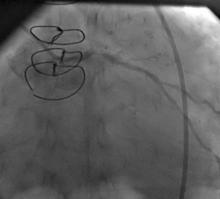

1) LM: subtotal ISR lesion (figure 2, figure 3)